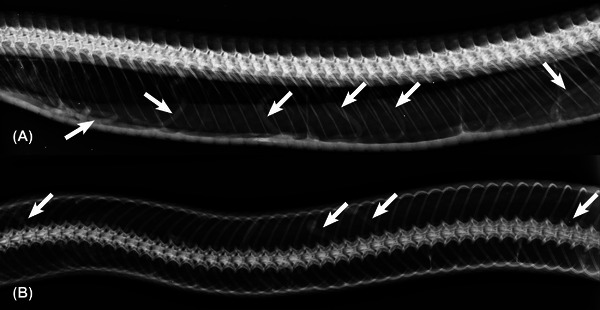

Pentastomids are parasites of the respiratory system of reptiles, birds, and mammals, where they can cause lesions resulting in the death of their intermediate hosts. This report describes radiographic aspects of pulmonary pentastomid infection in the Southern American bushmaster (Lachesis rhombeata). A female juvenile snake rescued in an urban area of the Northeast region of Brazil presented with lethargic behavior. Radiographic examination of the coelom cavity showed long cylindrical structures in the respiratory system with soft tissue radiodensity and width ranging between 4.0 and 5.0 mm. The next day, the snake died and was submitted to necropsy, where lung parasites were discovered, which were later identified as Porocephalus stilesi. A case of correlation between radiographic and macroscopic findings of pentastomid in snakes has not previously been reported.